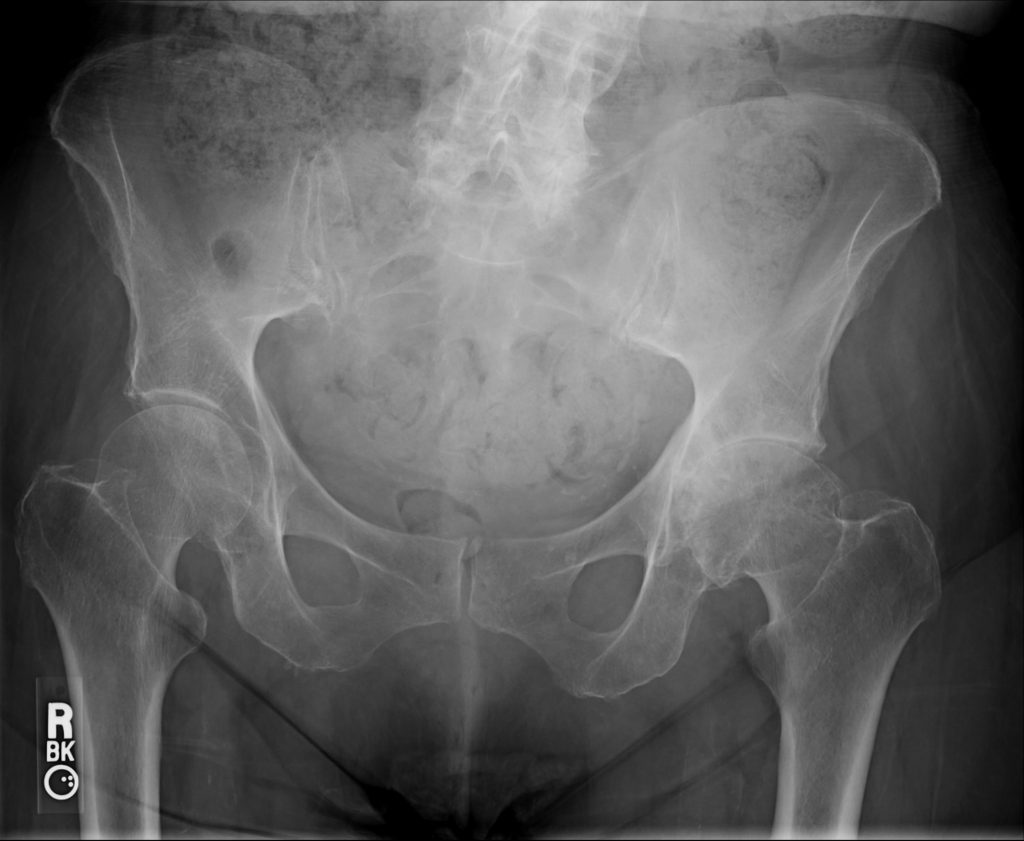

The diagnosis of hip arthritis can usually be obtained through a detailed history, physical exam and X-rays. The patient's history may include symptoms of groin pain, pain "deep in the joint", pain in a "c-clamp" distribution around the hip, thigh and even occasional knee pain. Physical exam may show limitations in range of motion and certain provocative measures can elicit pain in the groin. X-rays will show decreased joint space and even surrounding osteophytes from the femoral head or acetabular rim. On occasion, an MRI may be needed to confirm cartilage degeneration.